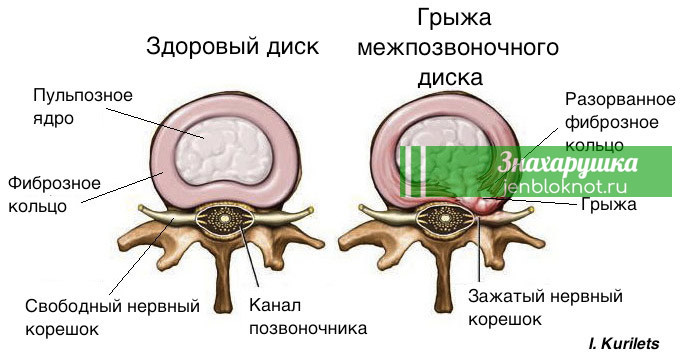

КТ-протрузии дисков: Визуализация и классификация